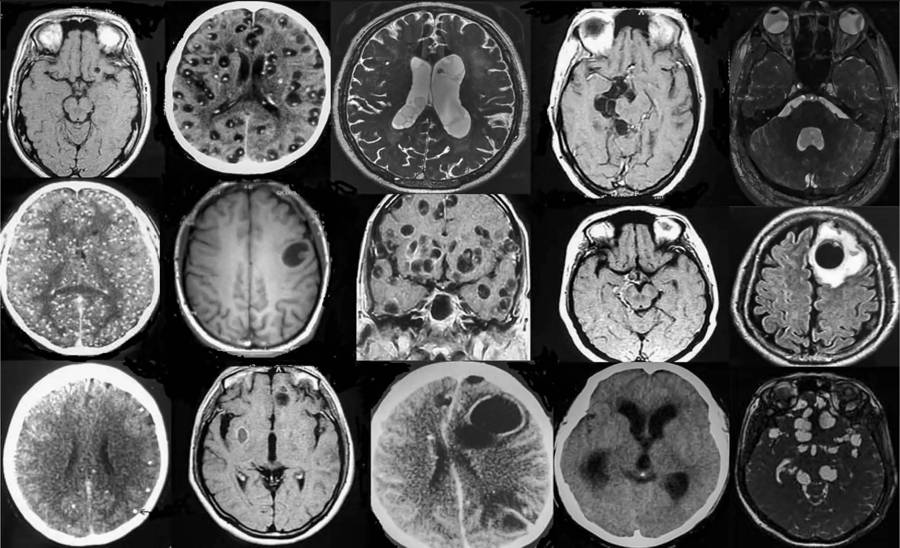

Durante el encuentro a distancia organizado por Sorbonne Université y el Centro de Estudios Mexicanos UNAM-Francia, la neuróloga detalló que el cerebro es el órgano afectado con mayor frecuencia por este padecimiento, aunque su gravedad es variable: “A veces es benigna con pequeños quistes, y otras puede ser muy grave, comprometiendo incluso la vida de los pacientes”.